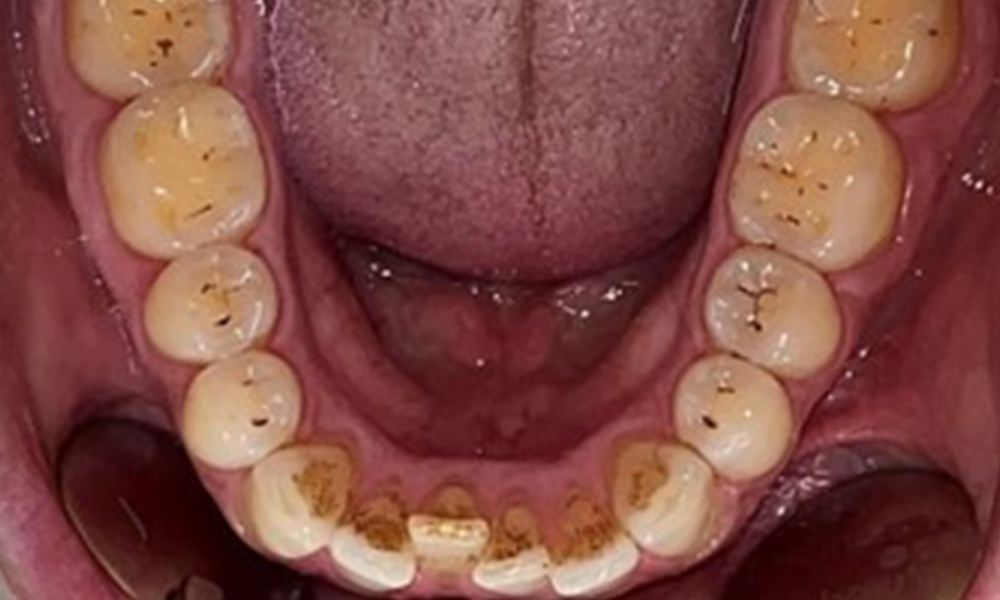

Instruction and motivation are important components of these appointments. Good home-based intraoral hygiene behaviour and understanding are important for patients. Plaque accumulation is particularly evident in the cervical regions (Fig. 8).

The arrows indicate plaque accumulations in the cervical region

Fig. 8: The arrows indicate plaque accumulations in the cervical region, © Dr R. Krapf

These must be discussed with the patient, and improvements to the teeth-brushing technique must be practised. A soft toothbrush attachment is recommended for home-based intraoral hygiene due to the presence of erosions and attritions.